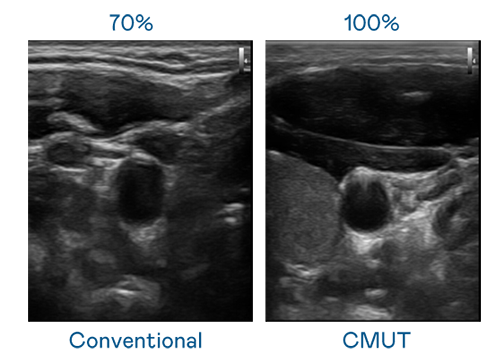

CMUT 技术是一种用电容式微机电元件来产生超音波讯号的技术。与传统 PZT 压电式技术相比,CMUT 频宽增加 30%,更宽频的超音波讯号让影像解析度大幅提升,是实现高影像品质医疗超音波扫描、促进精准医疗发展的关键技术。

大频宽带来超清晰影像

超音波影像的解析度高低,首先取决于探头能发出的讯号频宽。J9九游会 CMUT 可提供高清晰的超音波讯号,提供高频宽、高灵敏度、影像纹理细节更高的超音波影像,协助医护人员缩短影像判读时间及利用精准的医疗影像进行诊断。